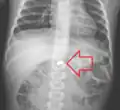

A coin seen on AP CXR in the esophagus -

AP X ray showing a 9mm battery in the intestines -